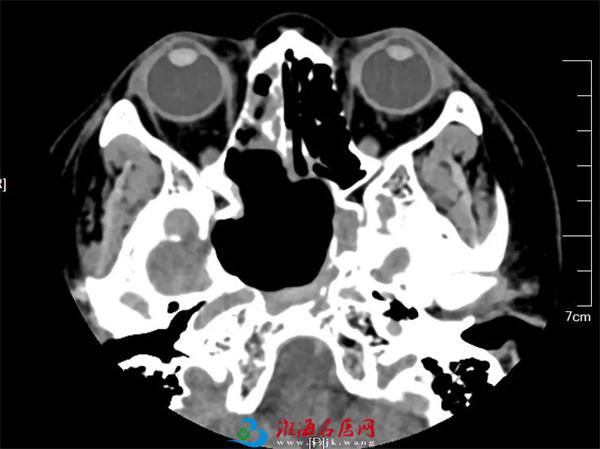

术前相关影像资料(黄圈:蝶窦巨大肿物)

术前相关影像资料

患者放心了,而王浩心里并不踏实。从影像学上看,蝶窦窦腔扩大,内见团片状异常信号影,TI、T2呈等、稍高信号影,增强扫描示:病灶两侧部分向外下突出,向上压迫颅底,周围骨质呈膨胀性改变,斜坡、蝶窦壁及两侧蝶骨局部骨质破坏,右侧视神经管局部骨质破坏,垂体受侵;CTA提示颈内动脉受压,与肿物紧贴。种种表现预示了手术风险。王浩坦言,拟定手术方案前,有两个难题摆在眼前。“一是肿物的性质(囊性还是实质性)不明确,性质不同,手术方式也截然不同。二是肿物已侵及周围颅底、垂体、视神经管及颈内动脉,手术难度大、风险高,术中一旦发生动脉破裂出血、脑脊液漏、视神经损伤等意外情况,很难单凭一科之力化解风险。”俗话说,一个好汉三个帮,关键时刻,兄弟科室提供了有力支持:经过反复读片、仔细甄别,经验丰富的影像专家曹伟认为可以排除恶性肿瘤,更倾向于真菌性病变;而神经外科、眼眶病及泪器病科、介入与血管外科的徐锋、戈振华、刘建等专家团队也明确表示,随时做好上台联合手术的准备。有了兄弟科室的鼎力相助,王浩心里踏实不少。